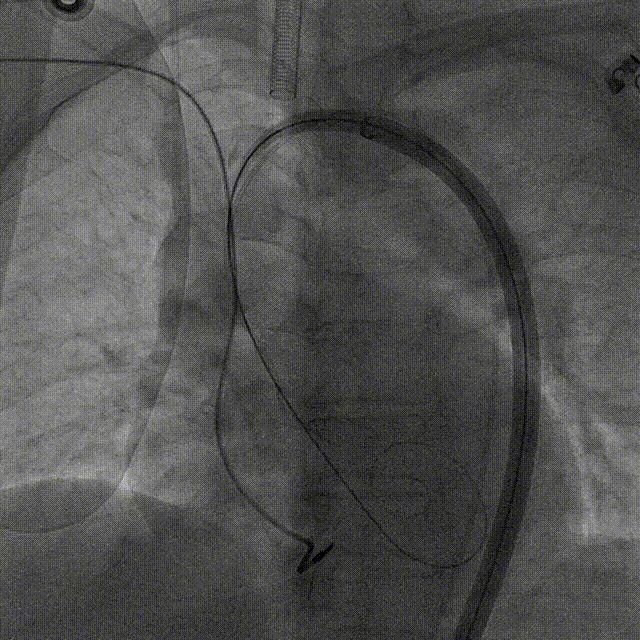

瓣膜对齐MARK

瓣膜调弯解离

瓣膜锚定键体位确认

瓣膜入窦

左窦确认

深度推进确认